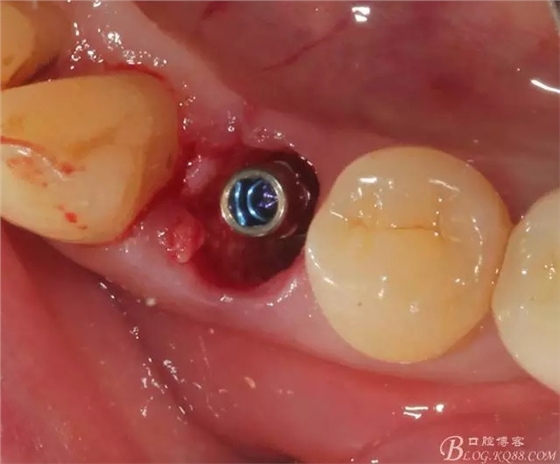

穩(wěn)定性還可以,就直接上了愈合基臺(tái)

頰側(cè)空隙塞了膠原塞 簡(jiǎn)單縫合,全程0翻瓣,很高調(diào)的告訴患者,術(shù)后不太會(huì)有反應(yīng)的。